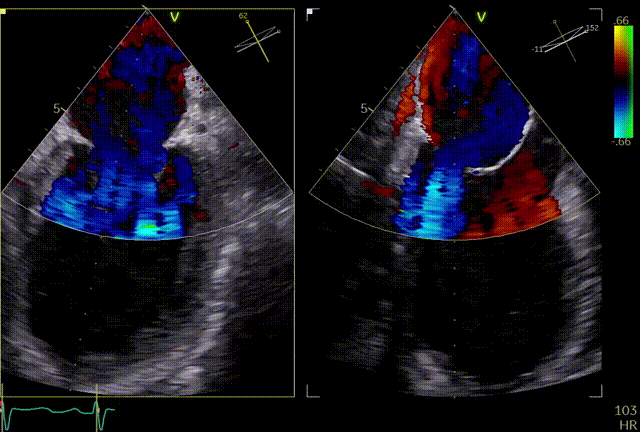

术前超声评估

二尖瓣前叶长度24.6mm,后叶长度15.3mm,脱垂宽度13.7mm、脱垂高度5.4mm,脱垂位置位于P2区域,有效瓣口面积5.64cm²。诊断二尖瓣重度关闭不全,考虑DMR。

术前TEE显示重度二尖瓣反流,确认二尖瓣后瓣(P2)脱垂

术后超声评估

术后TEE显示二尖瓣双孔化形成,瓣膜夹稳定